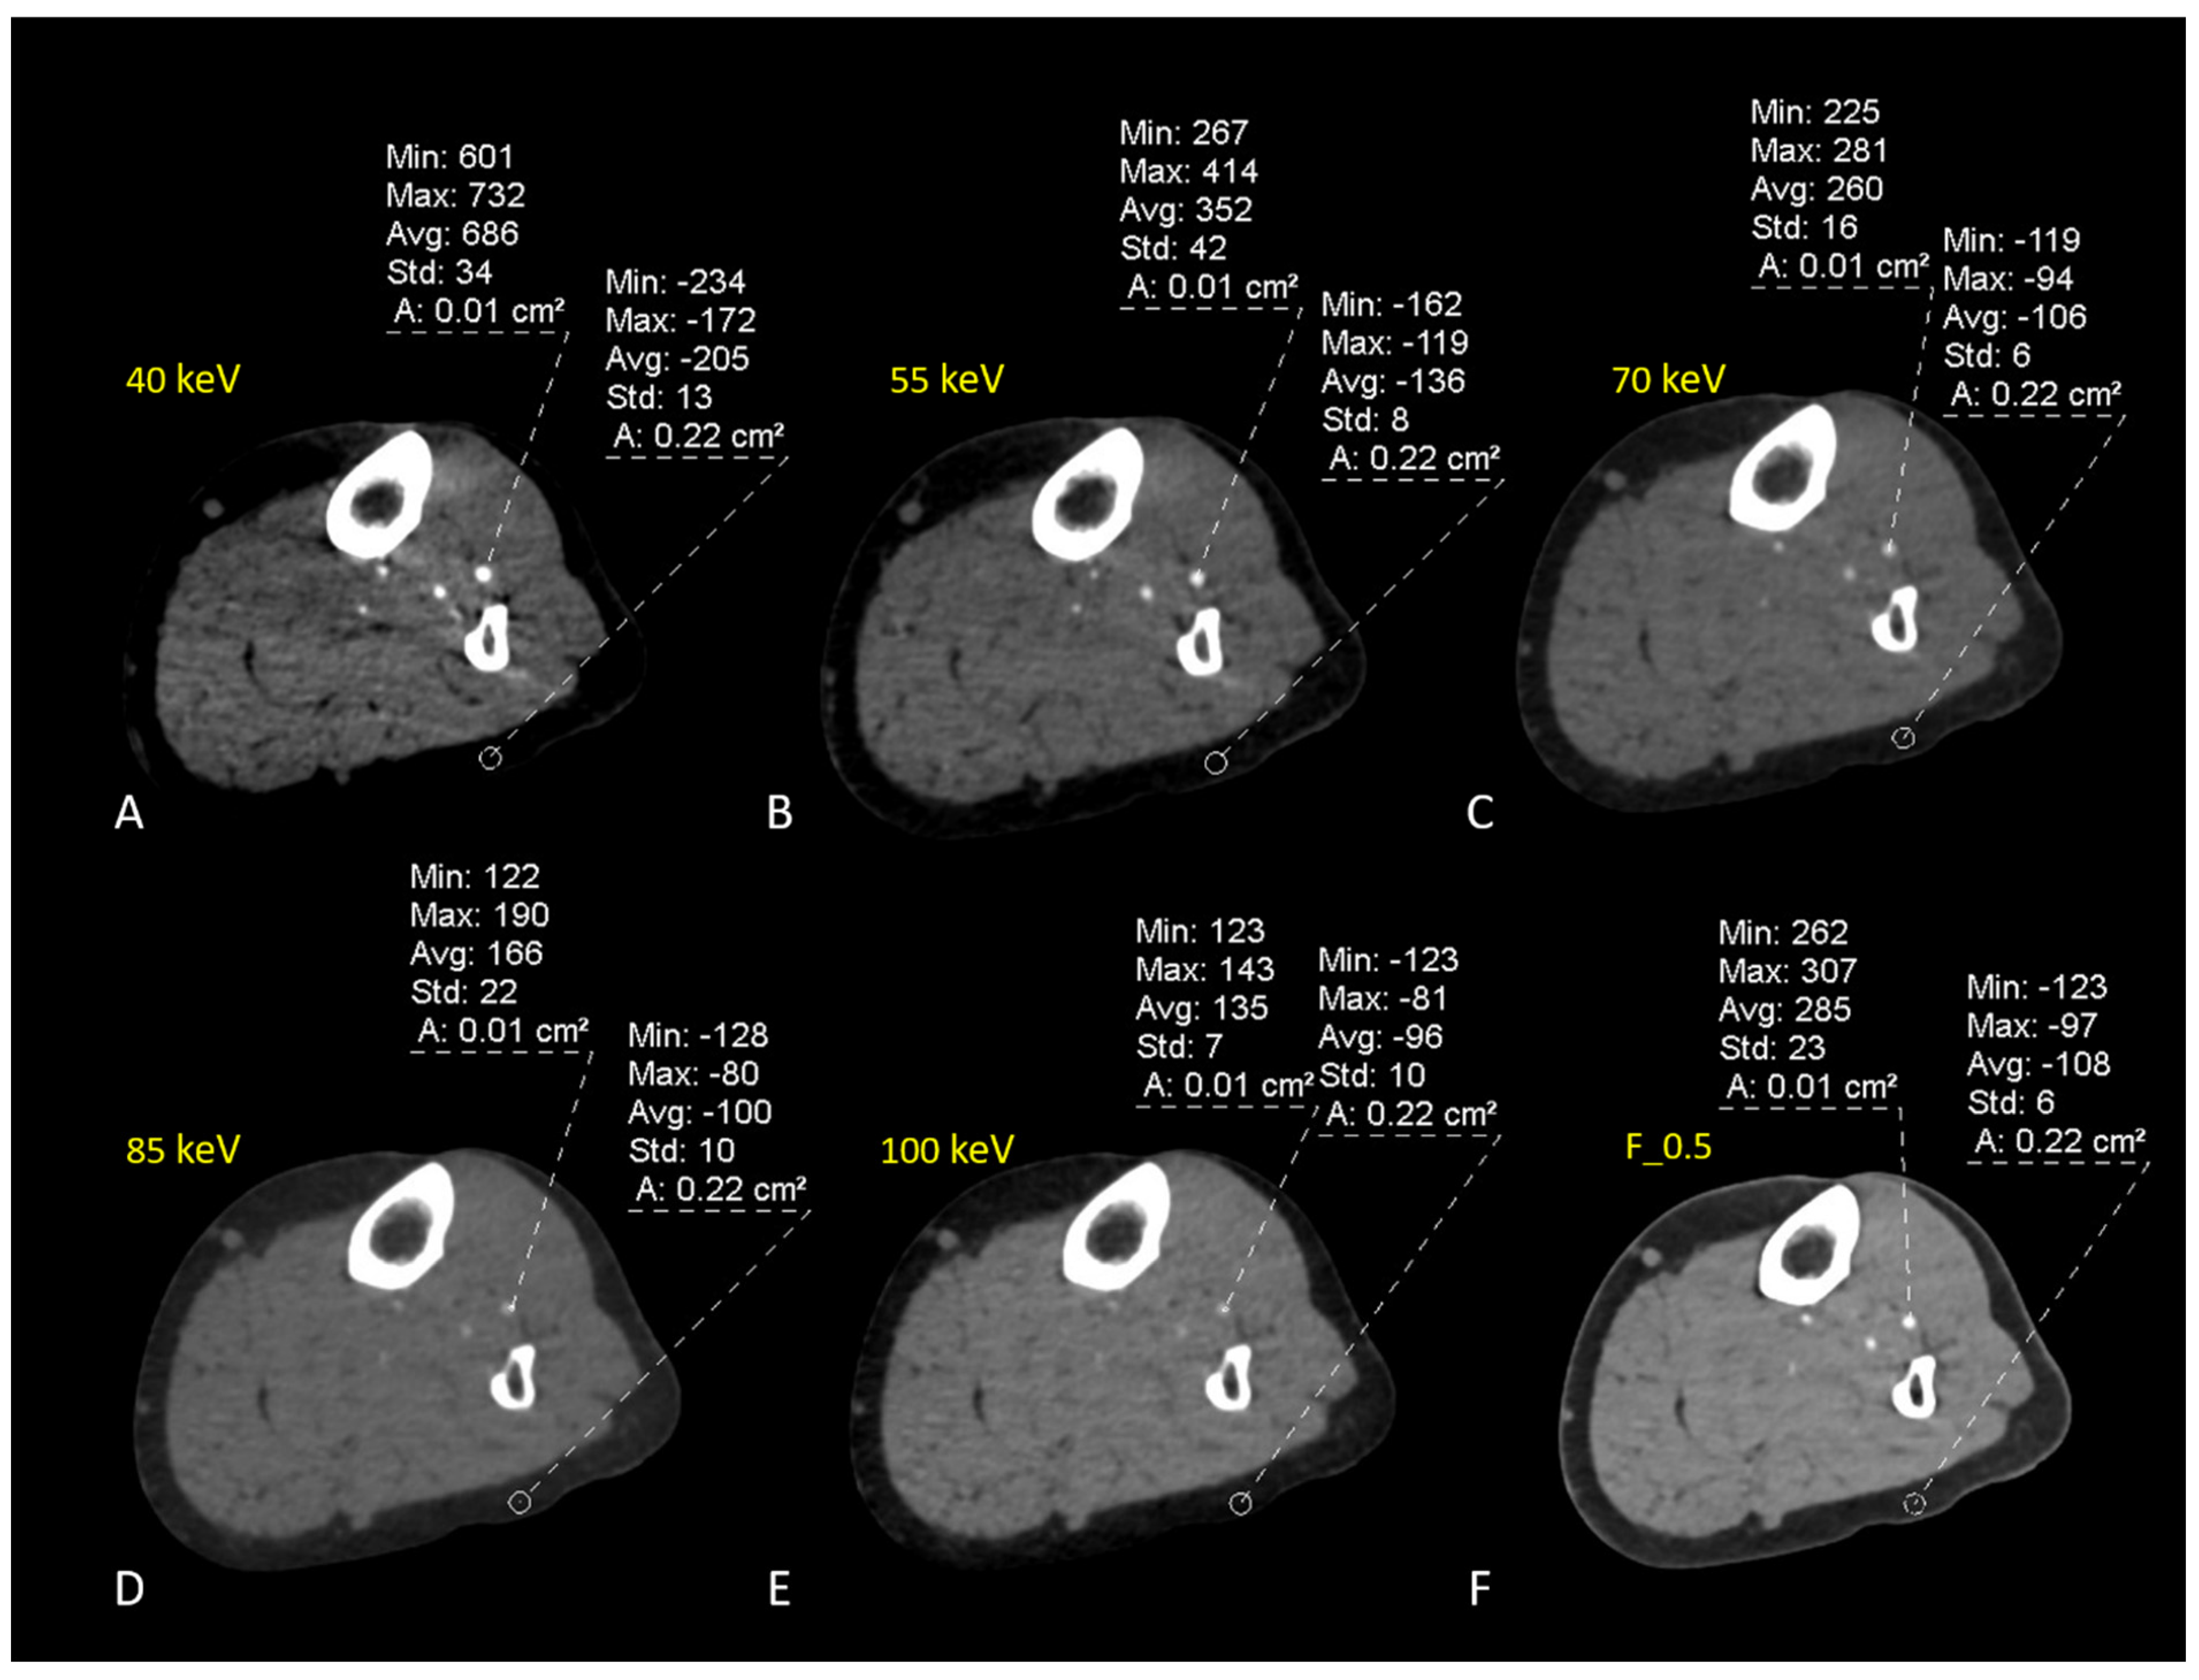

| Parameters | 40 keV | 55 keV | 70 keV | 85 keV | 100 keV | F_0.5 |

|---|---|---|---|---|---|---|

| Attenuations | ||||||

| ATA | 1174.97 ± 284.23 | 654.73 ± 145.84 | 407.39 ± 84.02 | 281.43 ± 53.06 | 210.85 ± 36.14 | 249.43 ± 29.08 |

| FA | 1138.28 ± 319.33 | 636.71 ± 171.39 | 391.74 ± 102.12 | 273.76 ± 64.78 | 205.94 ± 46.09 | 259.21 ± 31.21 |

| PTA | 1227.97 ± 254.92 | 681.01 ± 136.60 | 419.15 ± 80.77 | 285.62 ± 52.81 | 209.79 ± 35.89 | 245.33 ± 29.95 |

| Average all vessels | 1180.41 ± 45.09 | 657.48 ± 22.28 | 406.09 ± 13.75 | 280.27 ± 6.01 | 208.86 ± 2.58 | 251.32 ± 7.13 |

| Noise | 40.34 ± 5.72 | 28.97 ± 5.57 | 21.36 ± 4.60 | 19.64 ± 3.25 | 19.92 ± 2.99 | 20.75 ± 5.48 |